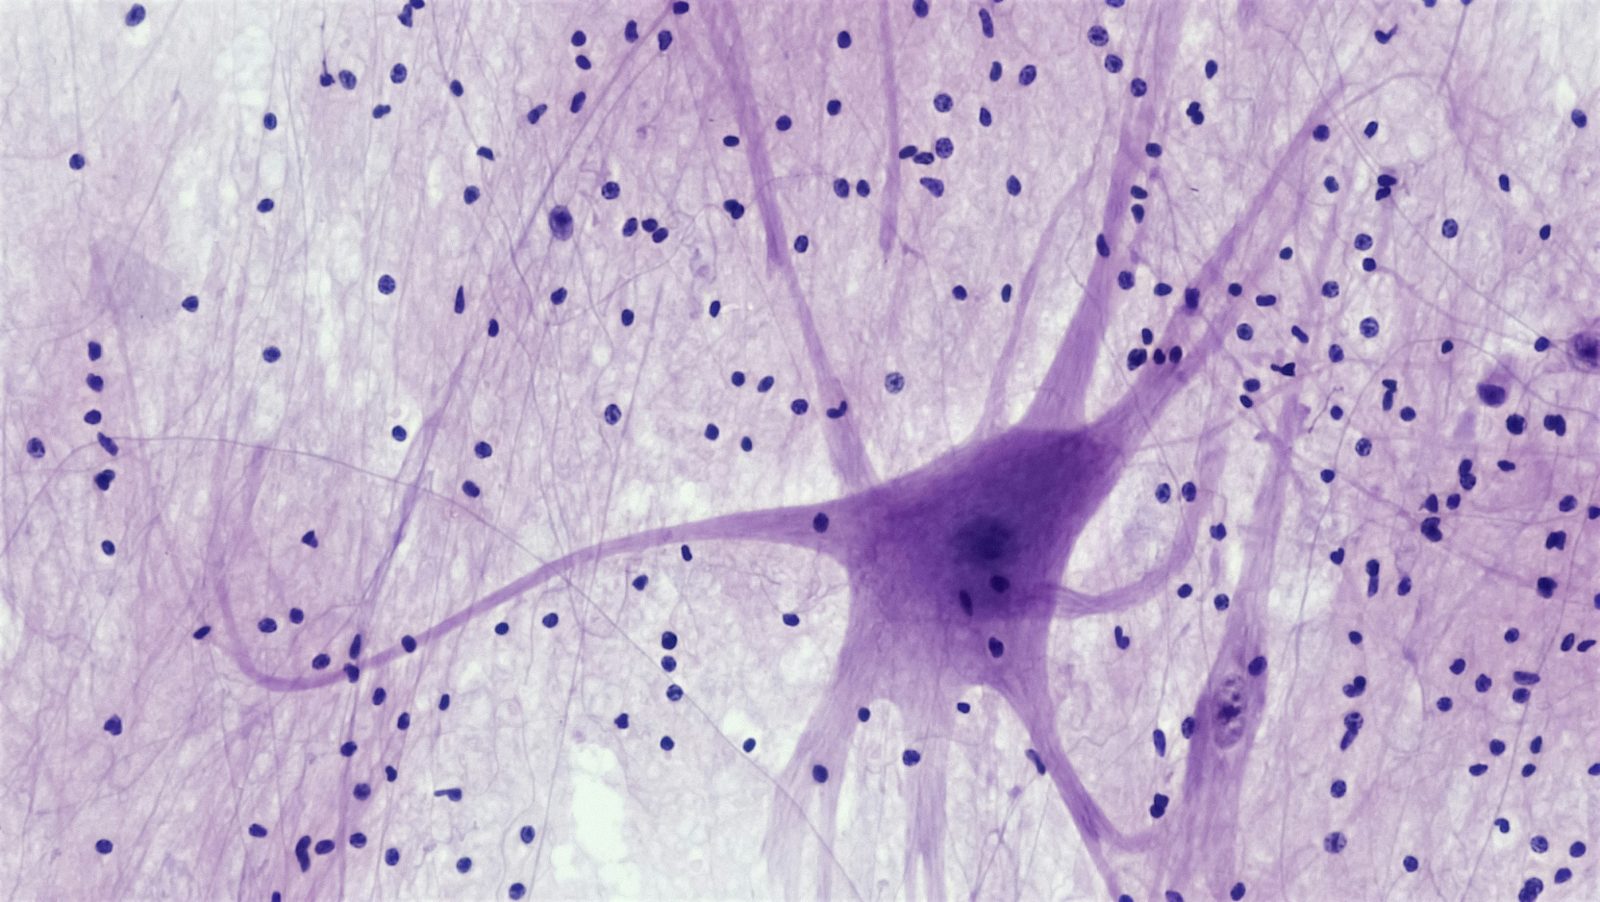

Investigadores descubren cómo las neuronas están conectadas para unir conceptos aparentemente no relacionados.

Un reciente estudio publicado en la revista *Neuron* revela un importante descubrimiento sobre cómo las neuronas están interconectadas para unir conceptos aparentemente no relacionados. Este mecanismo cerebral es crucial para mejorar la capacidad del cerebro humano de predecir lo que percibe basándose en experiencias pasadas. El hallazgo, realizado por investigadores de la Fundación Champalimaud y apoyado por la Fundación la Caixa, se centra en cómo el cerebro construye una jerarquía de conocimientos en la que conceptos de orden superior están vinculados a características más simples.

El estudio se realizó en ratones, criados en diferentes condiciones de luz, para observar cómo las conexiones neuronales se organizan en función de la experiencia visual. Los resultados mostraron que los ratones criados en la oscuridad desarrollaban conexiones neuronales más precisas en las áreas visuales del cerebro, mientras que en aquellos expuestos a luz regular, estas conexiones eran menos exactas pero ofrecían mayor información contextual, mejorando la capacidad de percepción.

Uno de los aspectos más destacados es el papel crucial que juega la experiencia visual en la organización de las proyecciones de retroalimentación dentro del cerebro. Estas proyecciones conectan áreas superiores e inferiores del sistema visual, y se ajustan según la experiencia, mejorando la integración de la información visual y permitiendo al cerebro formar una representación más precisa del entorno.